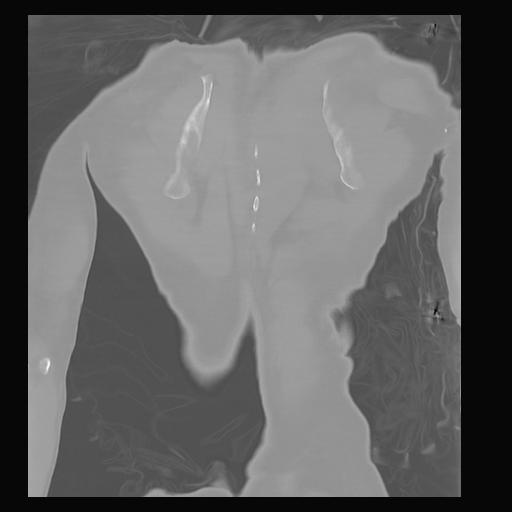

32 PULMON,CE,Coronal,3.000,PULMON,Coronal,